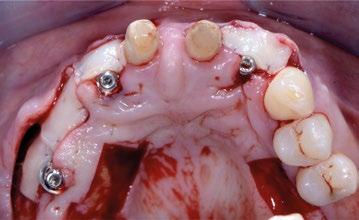

Se comienza con la exodoncia del 2.1 de forma atraumática y el legrado minucioso del alveolo. Para asegurar la correcta remoción de restos epiteliales de la bolsa periodontal se realiza curetaje rotatorio a baja velocidad con fresa de diamante de grano grueso (aro verde). (Figuras 4 y 5). Para llevar a cabo la regeneración ósea guiada se facilita el acceso tunelizado, mediante dos incisiones VISTA modificadas a nivel de la mucosa alveolar de 13 y 23, de las membranas reabsorbibles así como del injerto de tejido conectivo. A nivel de 1.1 se hace una incisión circular sin descargas a modo de ojal supracrestal.

Una vez desbridados los tejidos cicatriciales y de granulación de ambos defectos y habiendo minimizado la tensión de todo el tejido mucoso diseccionando a espesor total y parcial el túnel se procede a colocar ambos implantes en la posición 3D ideal teniendo como referencia la futura posición de los márgenes gingivales de 1.1 y 2.1. Así, la plataforma de ambos Prama se colocan a 1,5 mm apica -

les del futuro margen ideal. Esta longitud sabemos que será suficiente para conseguir un perfil de emergencia gingival que confiera un aspecto natural a nuestras restauraciones.

Apical a esta plataforma queda un cuello tratado específicamente (UTM) para su convivencia con el conectivo supracrestal mejorando la estabilidad de dichas futuras fibras gracias a la convergencia a coronal de los 3 mm de cuello y que en los primeros estadios de cicatrización aportan espacio para el biomarterial y el injerto de tejido conectivo sin que existan presiones nocivas (Figuras 6 y 7).